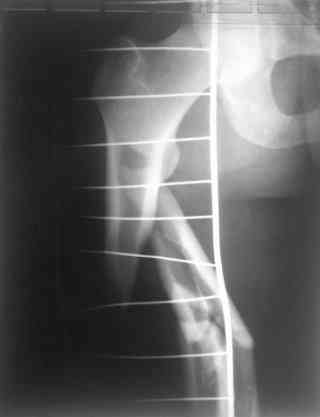

Надеюсь сейчас показать перелом, а потом синтез.